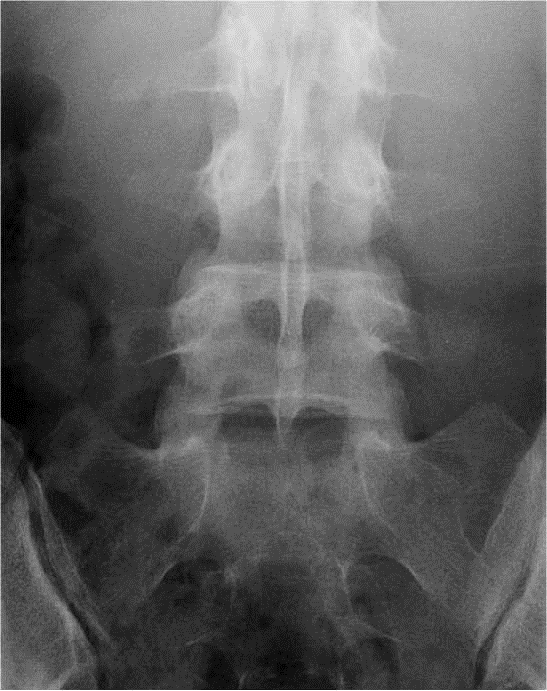

FACE

– – Le patient est en position rectitude de face

– – Il est en antéro-postérieur

– – Le dos contre la plaque

– – Il est déchaussé, les talons contre le plan de la table

– – Il est debout

– – Le plan sagittal médian est perpendiculaire au

RAYON DIRECTEUR

– – Il est centré sur L3

CRITERES DE REUSSITE

– – On doit voir les 5 vertèbres

– – Les apophyses épineuses doivent être alignées

– – Les articulation inter-vertébrales doivent être bien enfilées

ANATOMIE RADIOLOGIQUE

- – Articulaire supérieure

- – Pédicule

- – Apophyse transverse

- – Articulaire inférieure

- – Epineuse

- – Bord postérieur du canal rachidien

- – Bord supérieur des lames

- – Bord inférieur des lames

- – Isthme

- – Trou de conjugaison

- – Disque inter-vertébral

IMAGE NORMALE